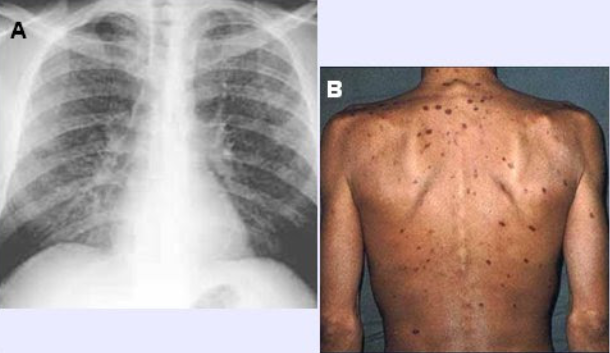

Diego es un niño alamos

Patrón radiológico: Diseminación difusa y puntilleo en todos los pulmones “alpiste de los canarios”, “semillitas cafés”.¿Que tratamiento le vas a dar?

A

Dotbal (RIPE)

rifampicina, isoniazida piranzinamida & etambutol o estreptocina

10 W x 4 tabletas 1 dosis

TB o Hongos! Mayor riesgo de meningitis tuberculosa.

A LA MADRE SE LE PASO LA BCG